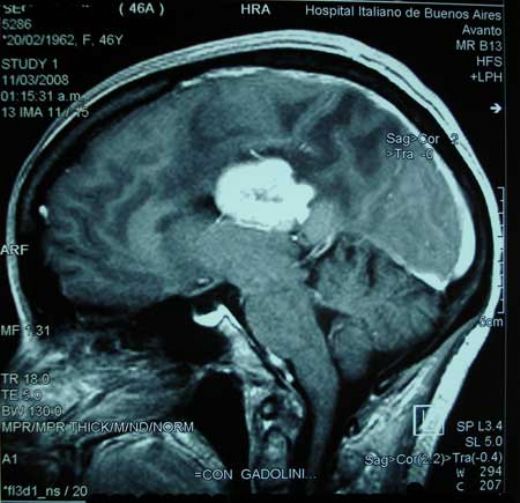

Beyinde kitle tanısı, genellikle bir dizi görüntüleme testi ve nörolojik muayene ile konulur. Bu süreçte kullanılan yaygın yöntemler şunlardır:

• Manyetik Rezonans Görüntüleme (MRG): Beynin detaylı görüntülerini sağlayarak kitlelerin boyutunu ve konumunu belirler.